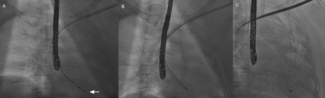

The authors report a case of early left atrial appendage occlusion (LAAO) device migration following the combined procedure of pulsed-field ablation and LAAO.